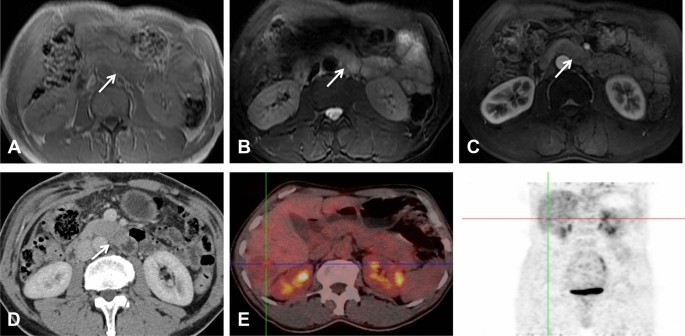

Preoperative diagnosis

The initial reported imaging diagnosis was a hepatic malignant tumor in one patient (case 1), malignant tumors of the pancreas in two patients (cases 3 and 4), pancreatic acinar cell carcinoma (ACC) and solid pseudopapillary neoplasm (SPN) of the pancreas in one patient each (cases 5 and 7), and neuroendocrine neoplasm in two patients (cases 2 and 6). In the patient initially diagnosed with hepatic malignant tumors (case 1), only MRI examination was performed prior to local resection of multiple liver lesions. MRI revealed multiple tumors in the liver, while the exogenous tumor in the uncinate process of the pancreas was located almost completely outside the pancreas; additionally, its signal and morphology could not be distinguished from that of the small intestine (Fig. 1). Furthermore, in the whole-body 18F-FDG PET/CT examinations, contrast was not taken up by the pancreatic lesion, and consequently, this pancreatic lesion was missed before surgery.

MRI, CT and 18F-FDG PET/CT images of a 37-year-old man with PB and multiple liver metastases. The exogenous mass in the uncinate process of the pancreas was isointense on T1WI (A) and hyperintense on axial fat-suppressed T2WI (B). In the AP, the enhancement of the tumors was lower than that of the surrounding normal pancreas (C). The above imaging findings of the tumors are similar to those of the surrounding intestines. On the PET/CT image (E), there was no radioactive uptake in the pancreatic tumor, and only one of the multiple metastatic lesions in the liver showed focal uptake (cross-hairs). (D) One month after the MRI scan, the CT scan revealed a cylindrical exophytic neoplasm of the uncinate process of the pancreas, similar to branches growing outward from a tree trunk.

In our study, the average tumor dimension was 4.1 × 6.3 cm (range 2.3 × 4.3 to 7.3 × 12.4 cm). Tumors were located in the head of the pancreas in three patients (42.9%), in the tail of the pancreas in two patients, and in the neck and body of the pancreas in one patient. On the MPR images, one of the lesions appeared round, and the other six (85.7%) appeared irregular in shape. All seven tumors were exogenous (100%), and six tumors (85.7%) grew outward from the pancreatic parenchyma, similar to branches growing from a tree trunk (Figs. 1D, 2C, 3A, 4B). Two of the tumors located in the head and neck of the pancreas showed a tapering head that extended into the hilum of the liver (Fig. 4B). In total, five tumors (71.4%) showed distinct margins (Fig. 1), and two tumors (28.6%) showed partly distinct or indistinct margins (Fig. 3C).

A total of six tumors (85.7%) were completely solid (Figs. 1, 2, 3, 4) with an average diameter of 5.28 cm, and one tumor showed mixed solid and cystic characteristics. No significant central necrosis was found. Calcification (Fig. 2A) was observed in one mass (14.3%). One patient exhibited hemorrhage, which presented as a high-density region on nonenhanced CT scans. Three tumors (42.9%) had thin, well-circumscribed, enhanced encapsulation (Fig. 2C). One patient exhibited a pancreatic head tumor with mild dilatation of the pancreatic common duct, and no patients suffered from pancreatic atrophy. Two tumors showed isointensity on T1-weighted imaging (T1WI) (Fig. 1A), while on T2-weighted imaging (T2WI), one tumor showed isointensity (Fig. 3B), and one showed hypointensity (Fig. 1C).

Compared with the adjacent normal pancreatic parenchyma on the noncontrast CT scan, six tumors (85.7%) showed isodensity (Fig. 2A), while one (14.3%) showed hypodensity. All tumors showed hypodensity in the AP (Fig. 3A). Four tumors (57.1%) showed hypodensity (Fig. 1D), while the other three (42.9%) showed isodensity in the VP (Figs. 2C, 4A). Six small tumors (85.7%), with an average diameter of 5.28 cm, showed homogeneous enhancement (Fig. 1D), while the large lesions showed nonhomogeneous and septal enhancement due to cystic necrosis; none of the tumors displayed ring enhancement. With dynamic contrast-enhanced MRI, all tumors (n = 2) showed hypointensity in the AP and portal phase (Fig. 1C), isointensity in the VP (Fig. 3C) as well as progressive enhancement.

18F-FDG PET/CT imaging showed no uptake in two pancreatic tumors (Fig. 1E); one of the pancreatic tumors was associated with multiple liver metastases, but only one metastatic lesion showed mild focal uptake (Fig. 1E). The third patient arrived at our hospital for surgical treatment after a PET/CT scan conducted at another hospital revealed a pancreatic head mass accompanied by increased FDG uptake (SUVmax = 4.22).